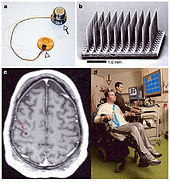

Using stereotaxy neurosurgeons can approach a minute target in the brain through a minimal opening. This is used in functional neurosurgery where electrodes are implanted or gene therapy is instituted with high level of accuracy as in the case of Parkinson's disease or Alzheimer's disease. Using the combination method of open and stereotactic surgery, intraventricular hemorrhages can potentially be evacuated successfully.[15] Conventional surgery using image guidance technologies is also becoming common and is referred to as surgical navigation, computer-assisted surgery, navigated surgery, stereotactic navigation. Similar to a car or mobile Global Positioning System (GPS), image-guided surgery systems, like Curve Image Guided Surgery and StealthStation, use cameras or electromagnetic fields to capture and relay the patient’s anatomy and the surgeon’s precise movements in relation to the patient, to computer monitors in the operating room. These sophisticated computerized systems are used before and during surgery to help orient the surgeon with three-dimensional images of the patient’s anatomy including the tumor.[29] Real-time functional brain mapping has been employed to identify specific functional regions using electrocorticography (ECoG)[30]

Surgery for chronic pain is a sub-branch of functional neurosurgery. Some of the techniques include implantation of deep brain stimulators, spinal cord stimulators, peripheral stimulators and pain pumps.

- Some forms of movement disorders (advanced Parkinson's disease, chorea) – this involves the use of specially developed minimally invasive stereotactic techniques (functional, stereotactic neurosurgery) such as ablative surgery and deep brain stimulation surgery